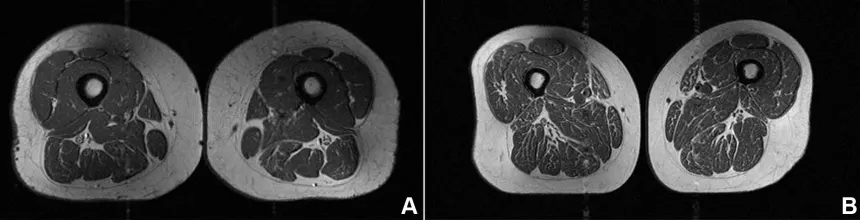

Στη μελέτη, μια δεύτερη γυναίκα 61 ετών εμφάνισε επίσης λιπώδη διήθηση στους μηρούς, αλλά σε μικρότερο βαθμό, με το 29% της διατροφής της να προέρχεται από υπερεπεξεργασμένα τρόφιμα.

Η γυναίκα με 87,1% υπερεπεξεργασμένα τρόφιμα στη διατροφή της (A στην εικόνα παρακάτω) είχε BMI 32,6 και χαμηλότερη φυσική δραστηριότητα από τη δεύτερη γυναίκα (B στην εικόνα), η οποία είχε BMI 31,8 και 29,5% υπερεπεξεργασμένα τρόφιμα. Παρ’ όλα αυτά, η πρώτη εμφάνιζε πολύ πιο έντονη λιπώδη διήθηση στους μηρούς.